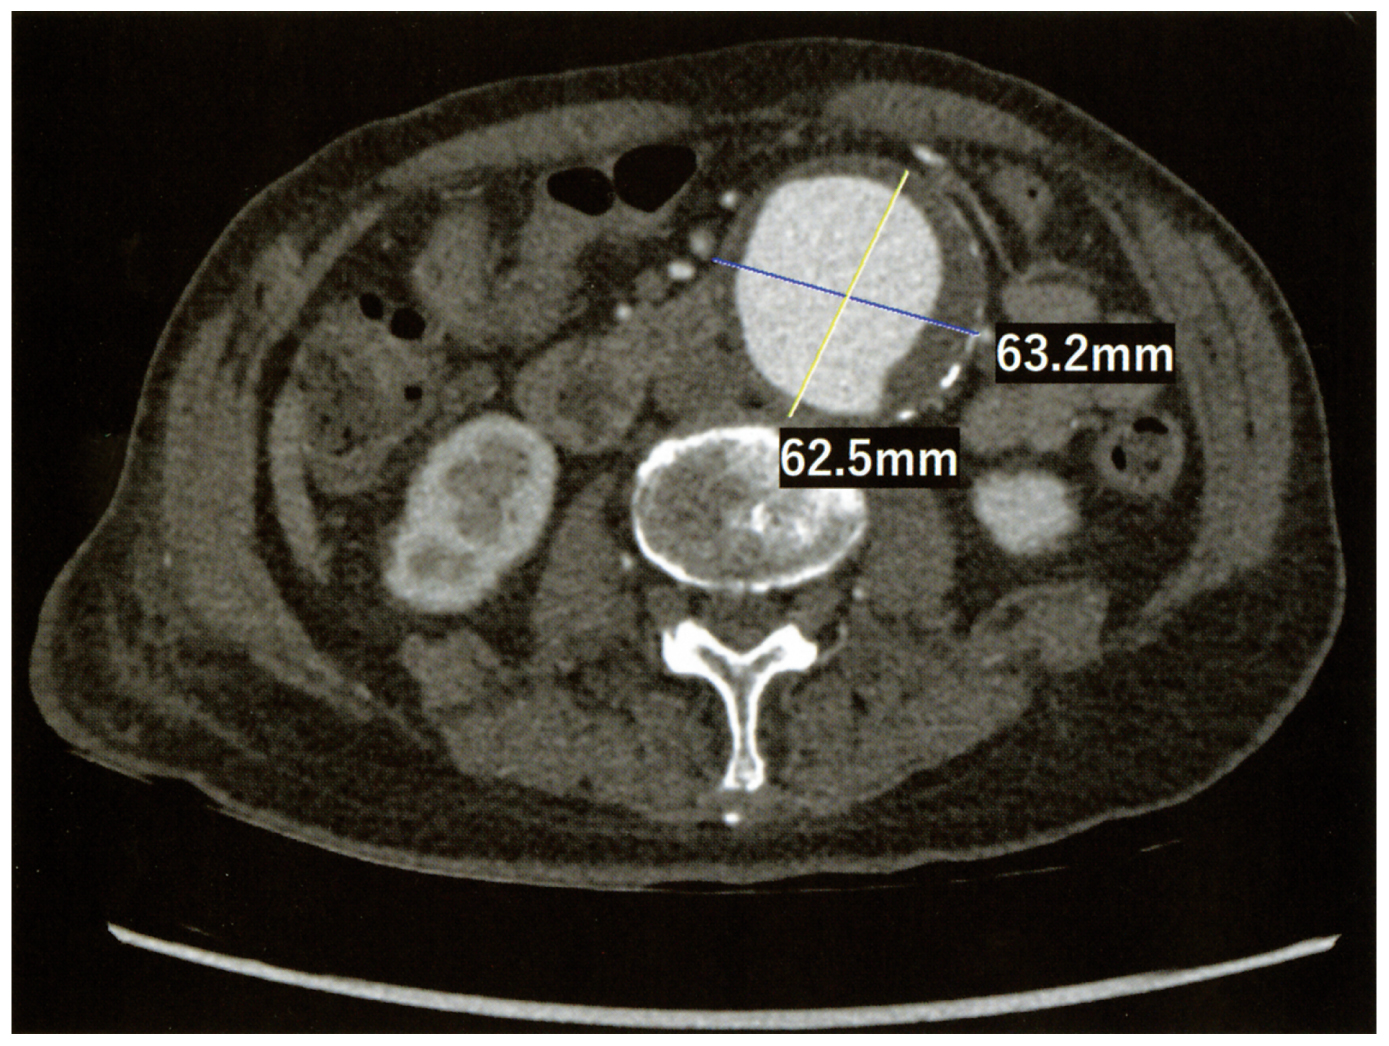

75歳の男性。健診の腹部超音波検査で異常所見を指摘され来院した。既往歴に,高血圧と脂質異常症がある。身長167cm,体重78kg。体温36.0℃。脈拍70/分,整。血圧134/80mmHg。頸静脈の怒張を認めない。心音と呼吸音とに異常を認めない。腹部は平坦,軟で,肝・脾を触知しないが,上腹部に拍動性腫瘤を触知する。両側足背動脈を良好に触知する。血液所見:赤血球468万,Hb 13.9g/dL,白血球8,300,血小板21万。血液生化学所見:尿素窒素20mg/dL,クレアチニン1.2mg/dL。CRP 0.2mg/dL。腹部造影CTを下に示す。